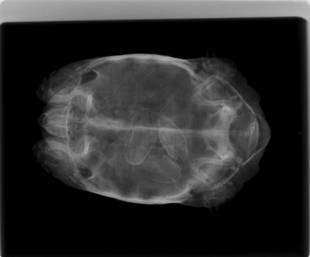

インドホシガメの手術